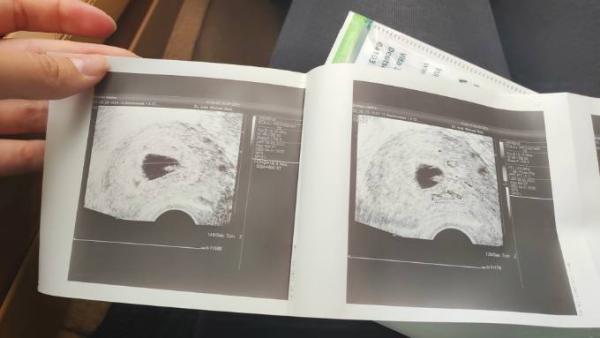

Da ich mir Ovulationstests getestet habe, müsste beim Eisprung am 10.5. Gewesen sein. 2 Tage davor haben wir es probiert. Also am 8. Und am 9.5. Und dann hat es auch geklappt. Wenn ich vom Eisprung aus rechne, wäre ich heute 6+6! Ich war bei 2 Kliniken und 2 Frauenärzte und alle sagten mir es sei eine gestörte Schwangerschaft.... Ich gebe immer mehr die Hoffnung auf. Ich würde eher einen natürlichen Abgang vorziehen aber was mach ich wenn der nicht kommt? Dann komm ich ja um eine AS nicht drum herum. Das Bild ist von Freitag letzte Woche und da war ich bei 8+1 ( normale Rechnung)

Der Dottersack ist wirklich sehr groß. Da müsste man eigentlich tatsächlich schon ein Baby sehen. Es besteht weiterhin die Möglichkeit das es ein Eckenhocker ist. Nächste Woche beim Termin müsste man dann aber endlich was sehen. Drück dir die Daumen! Man muss übrigens keine Blutungen haben. In der letzten SS war in der 8. Woche das Baby mit Herzschlag zu sehen. In der 12. Woche wurde mir gesagt, dass das Herz vor 3 Wochen aufgehört hat zu schlagen. Ich hatte keine Schmerzen, keine Blutung.. einfach gar nix..

Es heißt, dass man 11 Tage nachdem man einen Dottersack sieht auch einen vitalen Embryo sehen müsste, ansonsten kann man von einer avitalen Schwangerschaft ausgehen. Ein Dottersack über 6 mm Durchmesser ist auch eher kritisch zu sehen. Wenn es einen vitalen Embryo dazu gibt, heißt das nicht zwingend was, wenn nicht, dann wäre ich auch vorsichtig mit der Hoffnung. Wie ist denn der Unterschied zwischen den Terminen? Wann konnte was gesehen werden und wie lange schon?

Also ich kann dich leider auch nicht beruhigen, aber es sieht nach einer nicht intakten Schwangerschaft aus. Die Fruchthöhle ist sehr gut zu sehen und der Dottersack ist zu groß. Es müsste in der Woche eine Embryo zu sehen sein. Leider ist der Körper nicht immer gleich in der Lage dies zu erkennen und es wächst regulär weiter. Es tut mir leid.

Ich kann dich leider auch nicht beruhigen. In dieser SSW erkannte man bei mir immer einen Embryo mit Armen und Beinen (Gummibärchen) Für mich sieht es leider auch aus wie ein Windei :( Tut mir leid